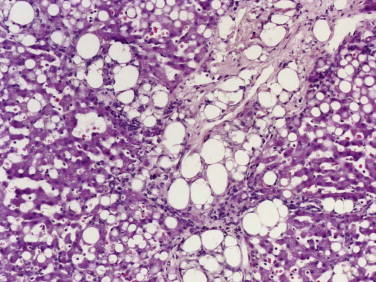

Dogs and cats with chronic gastritis often have persistent mucosal edema that matures into fibrosis. Concurrent inflammatory injury to the gastric glands is followed by regeneration that creates “nests” of hyperplastic glands embedded within the fibrous tissue (see “Atrophic Gastritis” section). It is also common to see the combination of fibrosis and glandular nesting with no evidence of active inflammation and no clinical history of gastric disease (Fig. 29-7 ). The glands within these nests usually have at least some degree of atrophy of the parietal cell mass with a relative increase in the prominence of the columnar mucus-producing epithelial cells. The combination of glandular atrophy, dysplastic repair, and mucus (intestinal) metaplasia represents a strong risk factor for progression to gastric carcinoma in people,11 an association that has not been proven in dogs.

Figure 29-7.